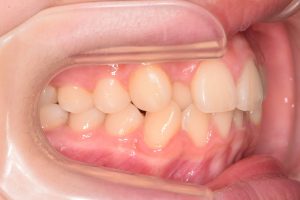

この患者さんは、初診時12才女性。

「上の前歯の中心がずれている」

「全体的に歯並びが良くないのが気になる」

ということで来院されました。

2期治療開始時(2024年11月)

左側